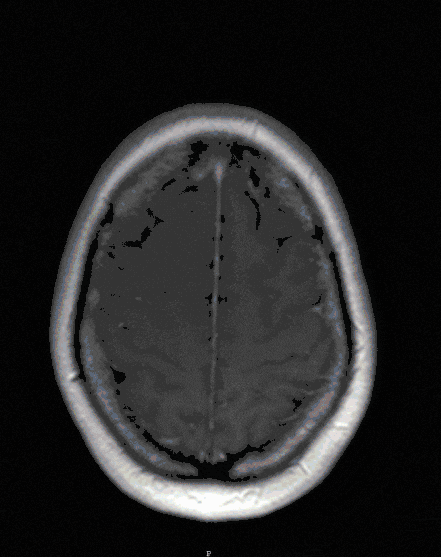

One of the most common diseases of the cerebellopontine angle is the so-called acoustic neuroma (actually vestibular schwannoma). However, meningiomas of the base of the skull (petrous bone, clivus, tentorium) can also develop here and lead to symptoms.

As tumors of the cerebellopontine angle are usually benign tumors, they can grow considerably in size due to their slow growth and thus threaten the brain stem with its cranial nerves.